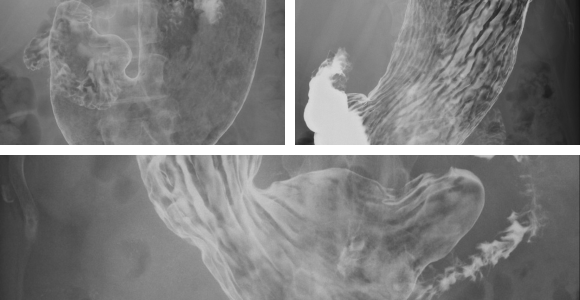

胃バリウム検査(上部消化管造影検査)とは、バリウムという造影剤を使用し、X線を用いて食道から胃、十二指腸までをリアルタイムで確認しながら撮影する検査です。消化管の形態(形や凹凸)の観察に優れており、粘膜の微細な変化やポリープ、がんなどを発見することができます。

粘膜の凹凸や形状の異常から、早期のがんや進行したがんを発見します。

バリウムが潰瘍のくぼみに溜まることで、その存在や大きさ、形を確認します。

胃の粘膜から隆起する小さなできものを発見します。

粘膜の荒れやひだの様子の変化から、炎症の有無や程度を評価します。

撮影台の上で体の向きを上下左右に変えながら、様々な角度から撮影を行います。胃の粘膜全体にバリウムを付着させるために、体を回転させていただくこともあります。